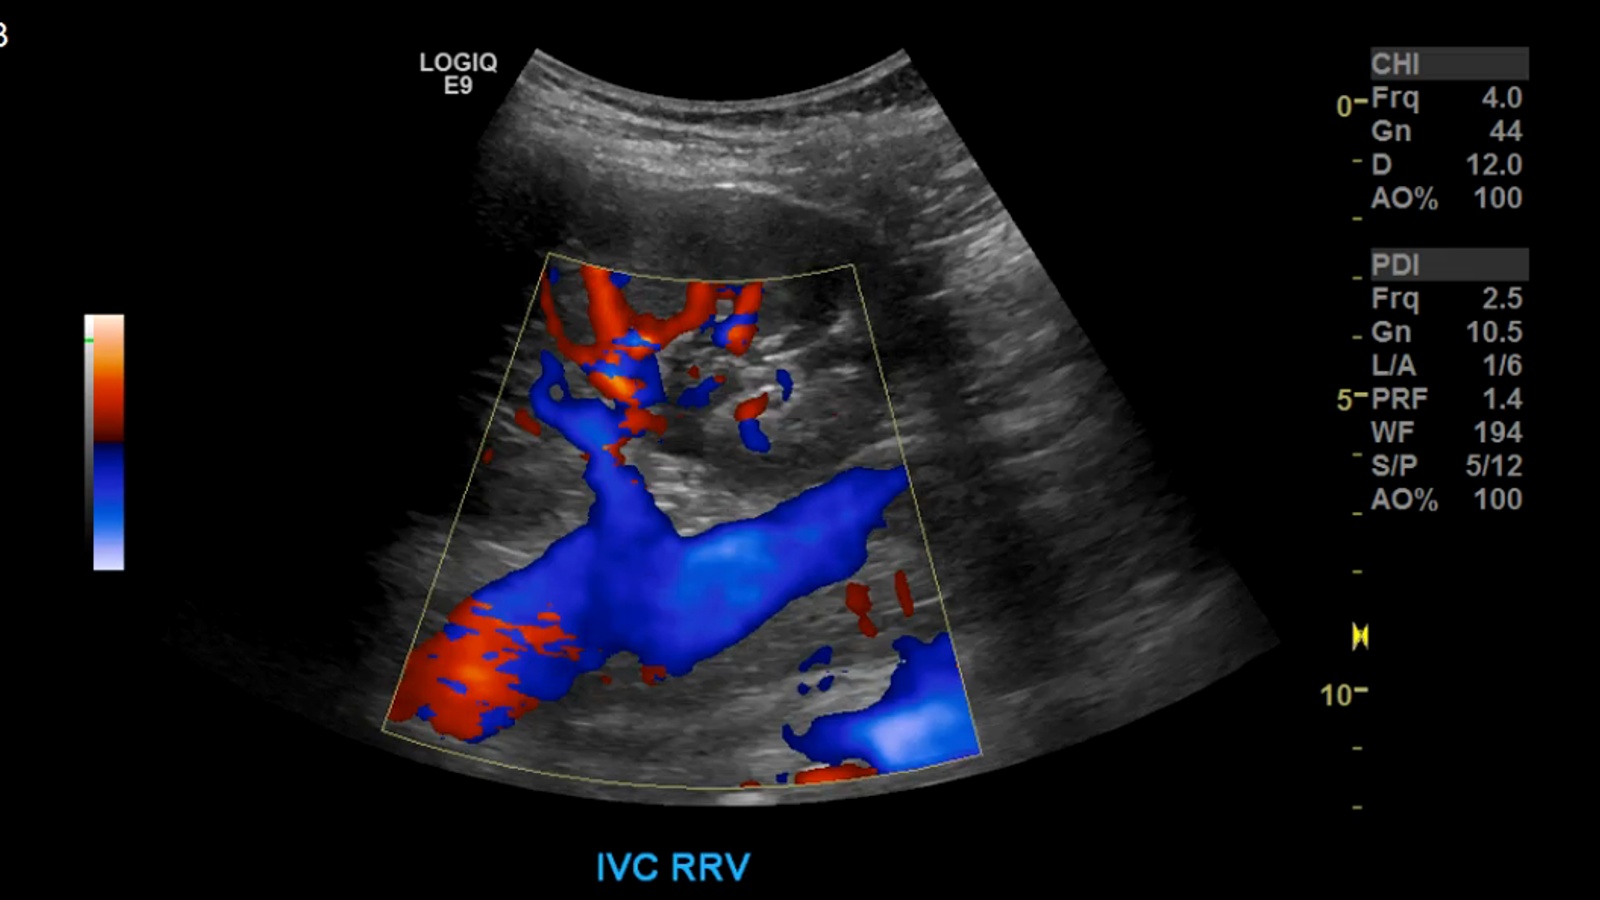

image39